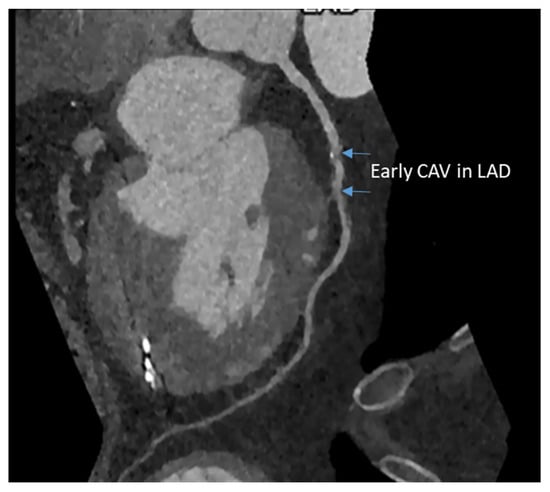

4. Computed Tomography Coronary Angiogram

CT coronary angiography (CTCA) has higher sensitivity and specificity for diagnosing CAV compared to stress echocardiography. It has been used in adults for routine detection of CVA with good image quality and low radiation dose [42]. With photon-counting CT, we are entering a new era that decreases radiation dose and less need for a contrast agent for CTCA to detect CAV early in the disease process [43]. The advantage of CTCA is that it is accessible in most centers, has a relatively low cost compared to MRI, and has high-resolution images. In addition, based on CTCA, 2010 ISHLT has decreased the stenosis of coronary to 50% rather previous 70% for early diagnosis of CAV [3]. The disadvantages are radiation exposure; contrast cannot be used with renal dysfunction and does not give any information on coronary microvasculature. CTCA is considered a gatekeeper for coronary angiography. An example of early detection of CAV in an 18-year-old HT recipient is shown in Figure 4. However, using CTCA in younger HT recipients has been challenging because of their high heart rate, small vessel size, and inability to lie still or hold their breath.

Figure 4. Early CAV in the left anterior descending coronary artery in an 18 yr old male six years after heart transplantation.